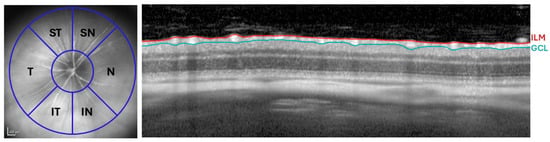

Automatic Retinal Nerve Fiber Segmentation and the Influence of Intersubject Variability in Ocular Parameters on the Mapping of Retinal Sites to the Pointwise Orientation Angles

The current study investigates the influence of intersubject variability in ocular characteristics on the mapping of visual field (VF) sites to the pointwise directional angles in retinal nerve fiber layer (RNFL) bundle traces. In addition, the performance efficacy on the mapping of VF sites to the optic nerve head (ONH) was compared to ground truth baselines. Fundus photographs of 546 eyes of 546 healthy subjects (with no history of ocular disease or diabetic retinopathy) were enhanced digitally and RNFL bundle traces were segmented based on the Personalized Estimated Segmentation (PES) algorithm’s core technique. A 24-2 VF grid pattern was overlaid onto the photographs in order to relate VF test points to intersecting RNFL bundles. The PES algorithm effectively traced RNFL bundles in fundus images, achieving an average accuracy of 97.6% relative to the Jansonius map through the application of 10th-order Bezier curves. The PES algorithm assembled an average of 4726 RNFL bundles per fundus image based on 4975 sampling points, obtaining a total of 2,580,505 RNFL bundles based on 2,716,321 sampling points. The influence of ocular parameters could be evaluated for 34 out of 52 VF locations. The ONH-fovea angle and the ONH position in relation to the fovea were the most prominent predictors for variations in the mapping of retinal locations to the pointwise directional angle (p < 0.001). The variation explained by the model (R2 value) ranges from 27.6% for visual field location 15 to 77.8% in location 22, with a mean of 56%. Significant individual variability was found in the mapping of VF sites to the ONH, with a mean standard deviation (95% limit) of 16.55° (median 17.68°) for 50 out of 52 VF locations, ranging from less than 1° to 44.05°. The mean entry angles differed from previous baselines by a range of less than 1° to 23.9° (average difference of 10.6° ± 5.53°), and RMSE of 11.94. Full article